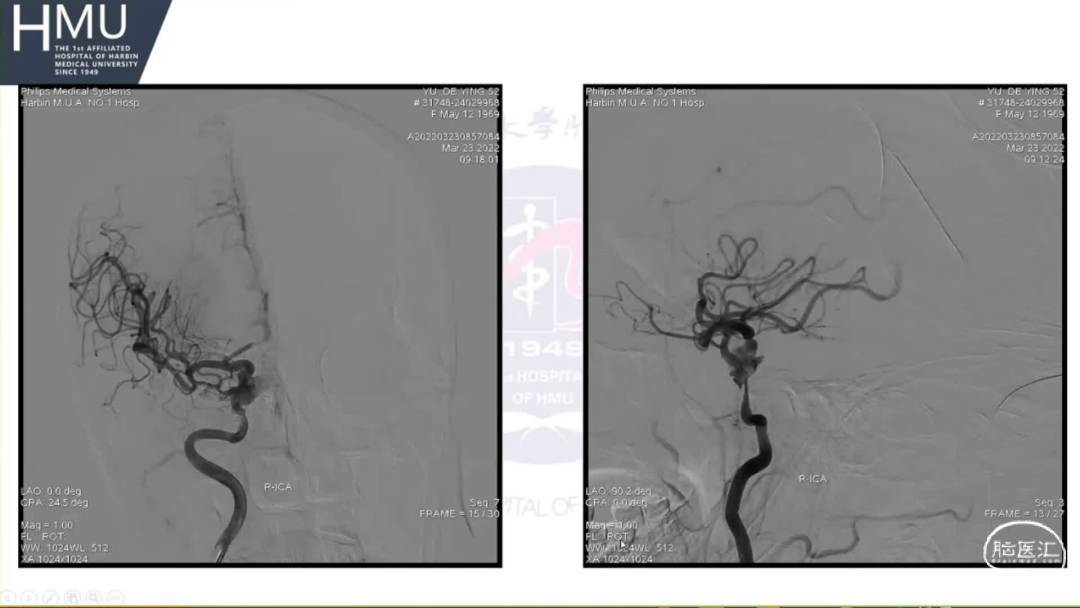

21:00覆膜支架置入术

海绵窦段动脉瘤如何导致蛛网膜下腔出血?

破裂致下腔出血可能因素

●大动脉瘤累及突破海绵窦硬膜